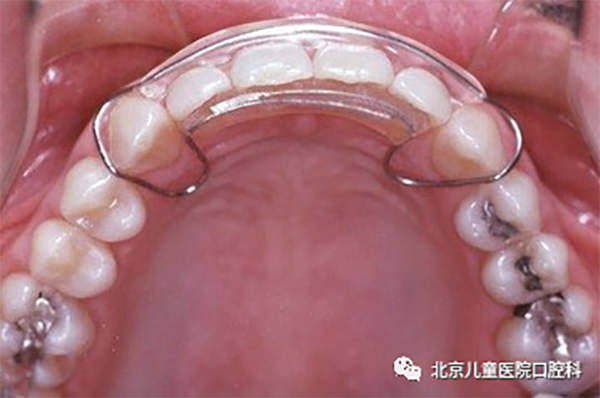

3、透明保持器:也称压膜保持器,因其透明美观及舒适度高,很多患者选择此类保持器。6-9个月后,常因损坏及染色而需要更换。